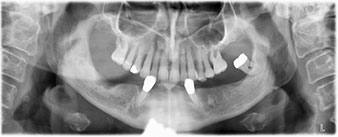

The 64-year-old patient presented with residual dentition of teeth 38, 33 and 43 and a clasp denture in the mandible (Fig. 1 and 2).

residual dentition

Fig. 2